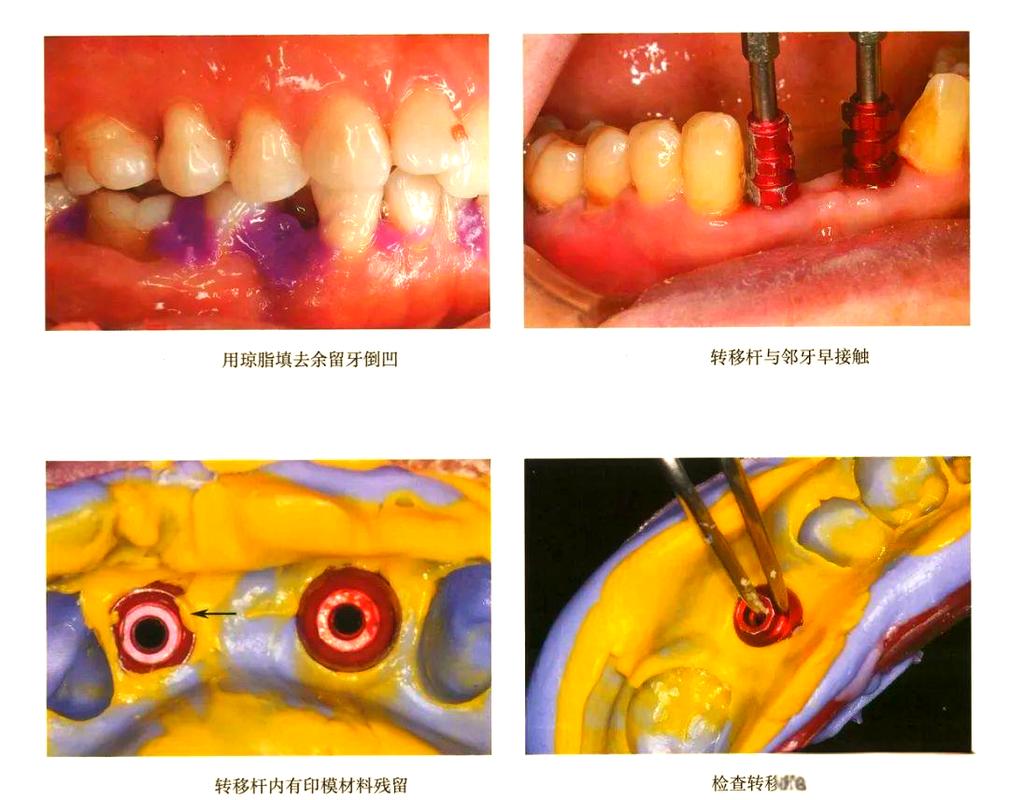

二次法印模技术:

- 原理: 在种植体完全骨结合后,先安装转移杆,取一个初步印模(通常使用开放托盘或简易托盘),然后从初步印模中取出带有转移杆的工作模型,在工作模型上安装替代体(Analog),最后将替代体连同转移杆一起放回口腔,使用个性化印模托盘进行最终印模。

- 优点: 对种植体上方基台高度要求较低(即使基台很低也可以);可以更精确地记录种植体周围软组织形态(如龈沟形态、位置),尤其适用于前牙美学区或需要精确复制软组织轮廓的病例;工作模型上可进行复杂的设计和调整。

- 缺点: 操作步骤多,耗时较长;增加了转移杆安装、替代体安装等环节,引入了更多潜在的误差来源;成本相对较高。

- 适用: 适用于种植体上方基台高度不足(<5mm)、需要精确记录软组织形态(如前牙美学区)、复杂病例(如全口种植、多单位复杂修复)或需要制作临时修复体的病例。